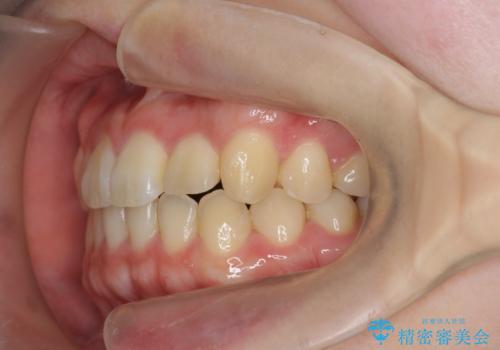

前歯のねじれを改善 小矯正+マウスピース矯正インビザライン

- 「前歯のねじれ、見た目を改善したい。」と矯正治療を希望され来院されました。

マウスピース矯正では改善の難しい前歯のねじれを前歯の部分ワイヤー矯正で改善したのち、インビザライン矯正を行い歯列を整えます。

インビザラインを行う前に前歯の部分矯正を行ったことで、しっかりとねじれが取れ整った歯列へと仕上げることが出来ました。